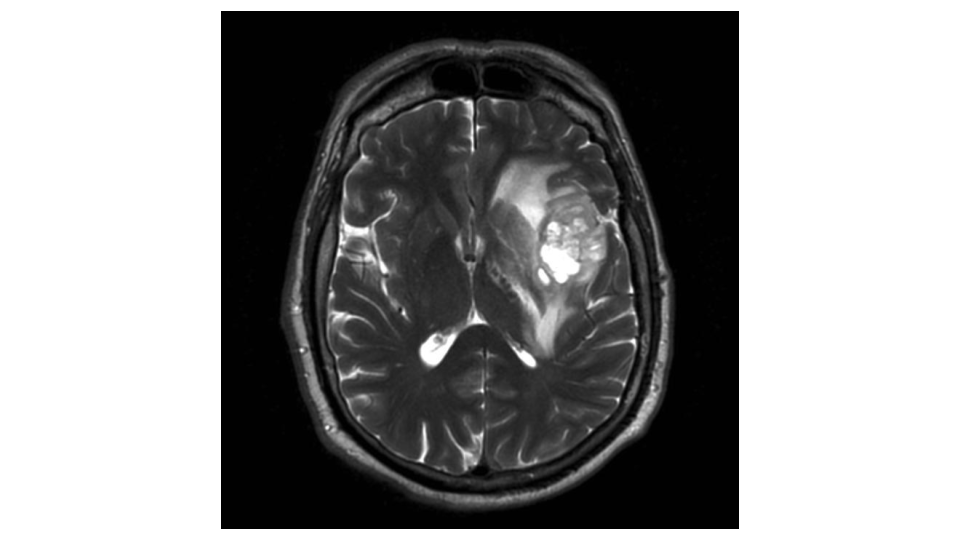

Suomessa todetaan vuosittain noin 900 aivokasvainta sekä lapsilla että aikuisilla. Aivokasvain on vakava tauti, josta voi kuitenkin selvitä. Aivokasvaimia on tutkittu useamman vuosikymmenen ajan, mutta tutkimuksessa ja hoidossa riittää edelleen haasteita. Tulevaisuudessa tekoäly voi mahdollistaa potilaiden yksilöllisen ja tehokkaamman hoidon. Dosentti Joonas Haapasalo johtaa aivokasvaintutkimusta, jossa tekoälyllä voidaan tunnistaa erilaisia vaikutustekijöitä aivokasvainten diagnosoimiseen ja hoitoon. […]